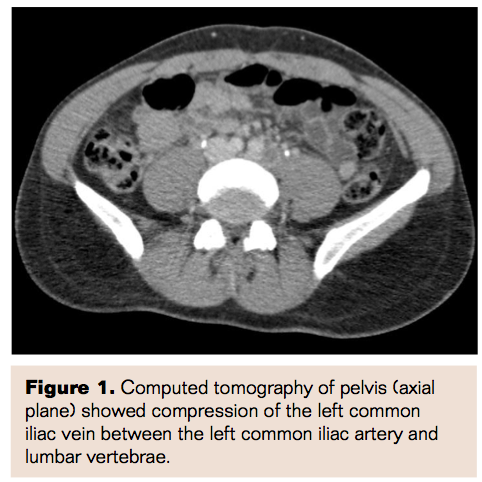

Considering the thrombus burden and increased risk of post-thrombotic syndrome, a decision to perform venous thrombectomy was made. Pelvic iliac venography was performed, which showed the D-IVC anomaly. A connection was noted between

the right common iliac vein and the left inferior vena cava (IVC). A decision was made at this point to deploy IVC filters into both right and duplicate left IVC in the infrarenal positions, as there was dynamic flow between the left IVC into the right IVC at both iliac and suprarenal levels. There was also left thoracic azygos flow from the left IVC. Two OptEase filters (Cordis Corporation) were deployed, with one in the left IVC and another in the right IVC in the infrarenal position. Venography performed after the deployment of filters confirmed the appropriate deployment level. Access was then obtained at the left posterior popliteal vein and a 5 Fr Cragg-McNamara thrombolytic infusion catheter (Covidien Inc) was advanced into the left common iliac position. Unfractionated heparin followed by tissue plasminogen activator (tPA) infusion (2mg/hour for 6 hours followed by 1mg/hour) was administered via the Cragg-McNamara catheter in an ICU setting for 24 hours.